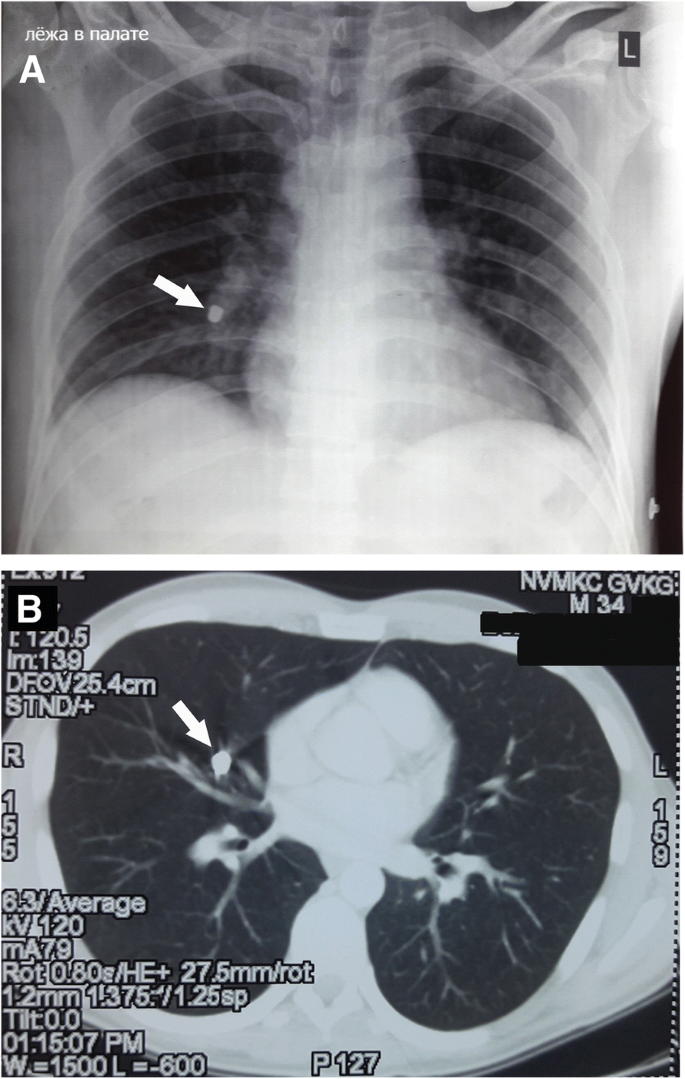

The US scan showed no dilatation of the inferior vena cava. Blood flow was retained, and a small volume of fluid in the right pararenal fatty tissue was identified. To our surprise, CT analyses revealed a foreign body of metallic density of 9.5 × 6.5 mm in the middle lobe branch of the right pulmonary artery (Fig. 1). Considering the absence of entrance wounds at the chest, a migration of the metal fragment was suspected from the inferior vena cava at the time of suturing, considering the embolus type of the foreign body. Severe trauma and damage control tactics were taken into consideration, thus we decided not to remove the metal fragment immediately, but to postpone its removal until after stabilization of his abdomino-skeletal injuries.

Visualization of the metal fragment in the branch of the right mid-lobe pulmonary artery by spiral computed tomography (CT) scan on the third day after the injury. a A photograph of the two-dimensional reconstruction of the CT frontal view image with the projectile embolus in the right pulmonary artery (marked with an arrow); b A photograph of the two-dimensional reconstruction of the CT sagittal view image with the projectile embolus in the branch of the right mid-lobe pulmonary artery (marked with an arrow) (c) A photograph of three-dimensional reconstruction of the CT front view image showing the pulmonary artery with the projectile embolus (marked with an arrow); d A photograph of CT angiography illustrating the projectile embolus (marked with an arrow); e A photograph of three-dimensional reconstruction of the CT angiography illustrating projectile embolus (marked with an arrow); f A photograph of three-dimensional reconstruction of the CT angiography showing projectile embolus in the pulmonary artery (marked with an arrow)

During the 2.5 months after the injury, the fragment that migrated after the booby trap explosion in the right mid-lobe artery did not present any clinical manifestations. Meanwhile, our patient was diagnosed with bullous lung disease of the upper lobe of the right lung, thus the removal of the fragment was performed after our patient had completed the rehabilitation course. Our patient was admitted to the Department of Thoracic Surgery at the National Military Medical Clinical Center (Kyiv). A chest X-ray and CT scan showed no changes in the right mid-lobe pulmonary artery at the location site of the embolus from the booby trap fragment (Fig. 4). On August 17, 2017 (the 80th day after injury), our patient underwent a right-sided thoracotomy in the fifth intercostal space. On revision of the right lung, a firm metal object with a diameter about 10 mm was identified in the basal region of the middle lobe. The mediastinal pleura was incised, the branches of the right upper pulmonary vein were identified. The right pulmonary artery and the mid-lobe artery were taken to traction sutures (Fig. 5a). The booby trap metal fragment was identified in the lumen of the branch of the right mid-lobe artery at the medial segment, next to the bifurcation of the lobar artery. The wall of the artery was cut above the location of the metal fragment and a metal object 8 × 6 mm in diameter was visualized tightly fixed to the wall of the vessel (Fig. 5b). Analyses of the shape and kind of the embolus showed features of a piece of metal wire, which was a hand-made element that acted as additional shrapnel and was manually added to the conventional F1 hand grenade, to achieve a higher crippling effect against military personnel. Further, the distal lumen of the right mid-lobe artery was thrombosed, while the blood supply and aeration of the middle lobe of the right lung were preserved due to the collaterals. The embolus bed was washed with antiseptic, followed by ligation of the proximal and distal parts of the artery. An atypical resection of the upper lobe of the right lung was performed considering the presence of the multiple lung bullas up to 15 mm in the upper lobe of the right lung. After thoracotomy, our patient was administrated for ciprofloxacin 600 mg/day, ertapenem 1 g/day, and amikacin sulfate 1 g/day.